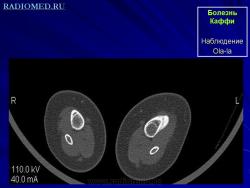

Каффи болезнь.

Каффи болезнь (m. Caffey), инфантильный кортикальный гиперостоз, семейный кортикальный гиперостоз, Каффи - Сильвермена синдром, Каффи - Смита синдром, Каффи - де Тони синдром.

Передается по доминантному типу, проявляется с рождения. Характеризуется повышением температуры, болью, отеком мягких тканей конечностей, недоразвитием длинных трубчатых костей (бедренной, большеберцовой, ключицы) и нижней челюсти. Рентгенологически определяются периостальные наслоения в области коркового вещества костей, которые с течением времени превращаются в костноподобные образования, располагающиеся по длиннику костей.